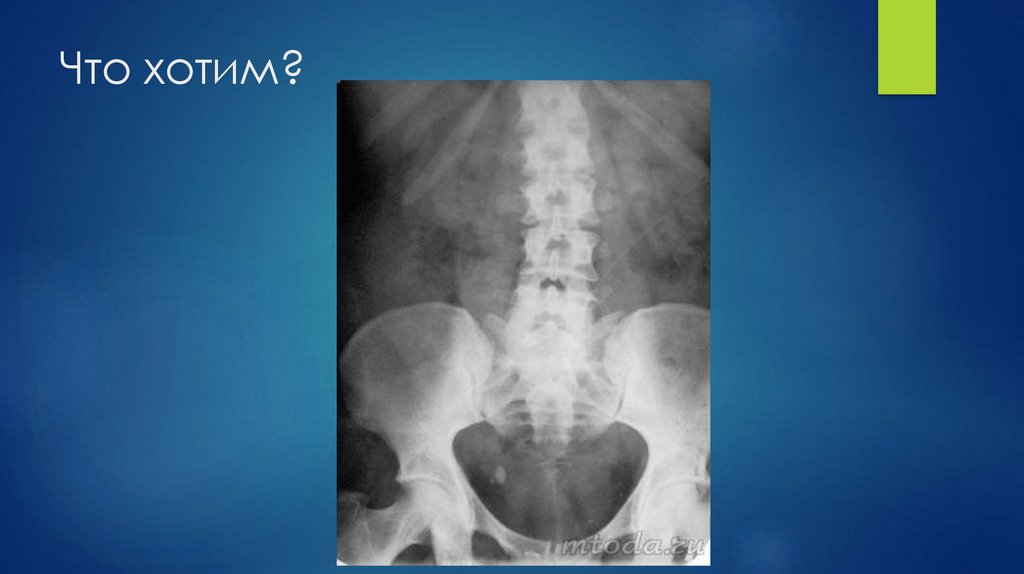

Что хотим?